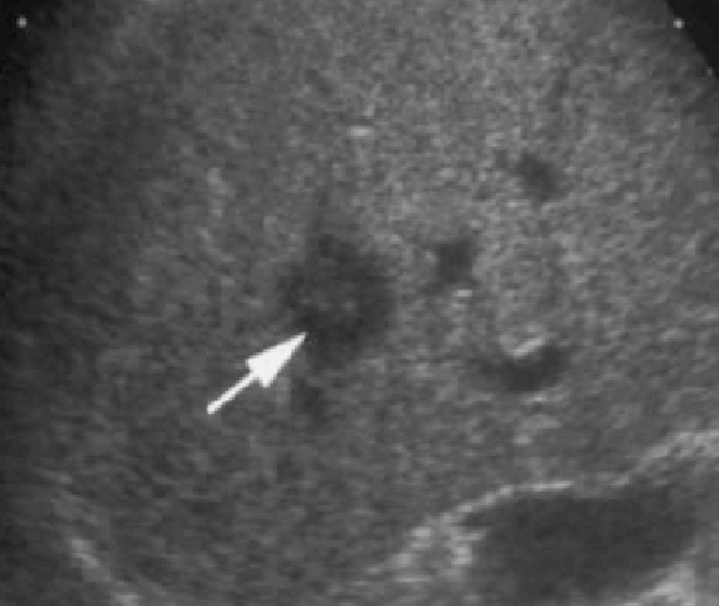

<2cm small hcc sono features ② 2~3cm hcc sono finding

- hypo-hyperechoic

- ireegular margin

- halo(+) 종양이 2cm 이상 커지면 주위조직을 밀게 되면서 피막이 형성되면서 저에코 테두리가 나타남. (간세포암의 40~50%)